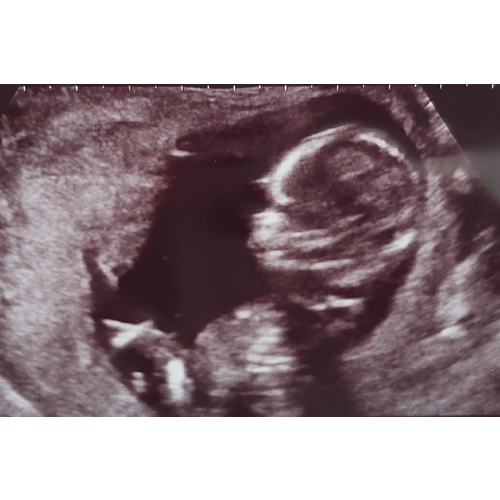

Reactie op Stefaniel

Liva hierbij de andere foto 馃槉馃

Ik hou het op jongen 馃挋馃槉